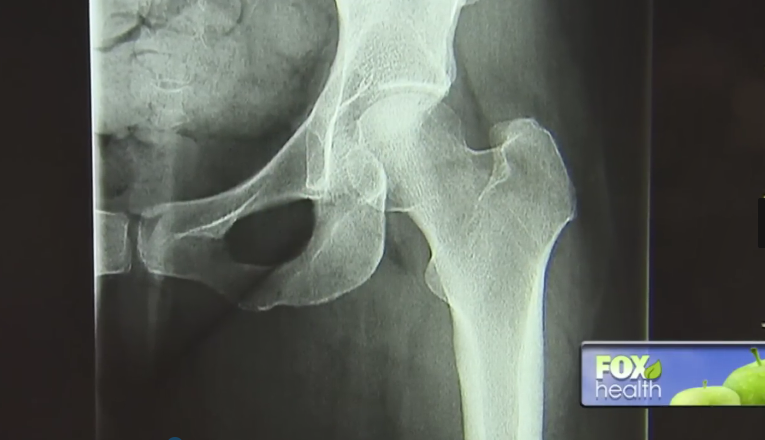

股骨头坏死,是一种因骨头“断粮”(血供受损或中断)引发的关节病变,可导致患者股骨头结构改变与塌陷,引起关节疼痛及行走障碍。

最开始是右臀部失去了知觉,珍妮不得不借助拐杖走路,可情况还在变糟糕,很快,她的左臀部也开始出现疼痛。她被确诊为股骨头坏死。

这种情况通常需要接受髋关节置换术,该方法始于上个世纪40年代,简单来说就是将受损的髋关节替换为人工假体,美国每年大约有15%的髋关节置换手术都是在拯救股骨头坏死。但珍妮拒绝了。